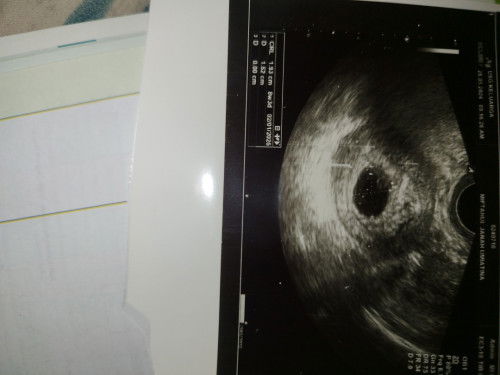

Usia 8week Usg Janin tidak kelihatan

Usia 8week tadi pagi abis usg kata dokter janin blm kelihatan cm ada kantung hamil nya doang dan sebulan kedepan di suruh balik usg lagi,ada yg pernah ngalamin kaya gini gak?#Sharing_dong_Bund apa itu normal mom?

itu di keterangannya CRLnya sudah 1.93 cm Bund, bukannya CRL itu artinya ukuran janin ya. kok dokternya bilang janinnya belum kelihatan